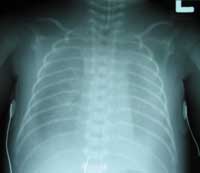

The x-ray shows moderate bilateral effusion.There is atelaectasis of the left lower lobe. Mild body wall edema is noted. The lungs display a normal vascular pattern.

BELOW is a follow-up X-RAY later the same day.

WHAT HAPPENED ? DO YOU WISH TO COMMENT?